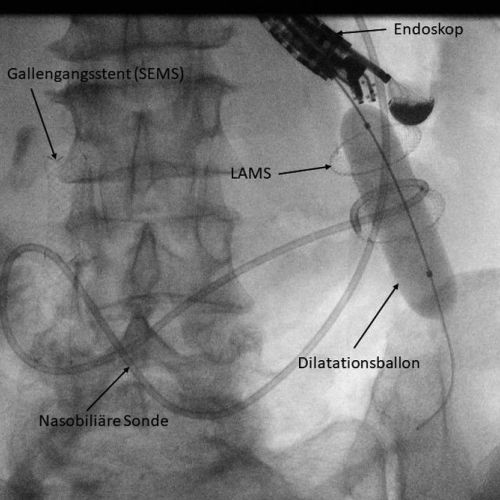

Schritt 2: Unter endoskopischer Sicht wird ein Führungsdraht durch die Stenose vorgeschoben und darüber eine Sonde in die Zielschlinge gelegt. Die Jejunalschlinge wird mit Flüssigkeit und Indigokarmin aufgefüllt. Die Flüssigkeit wird benutzt um die Jejunalschlinge zu entfalten und eine sichere Punktion zu ermöglichen. Das Indigokarmin wirkt später als Beweis, dass der Stent in die richtige Jejunalschlinge appliziert wurde.

Schritt 3: Anschließend wird ein LAMS direkt transmural in das Jejunum eingebracht. Um das zu erreichen, besitzen die bevorzugt angewendeten Stentapplikatoren eine elektrochirurgische Spitze (Abbildung 1). Das ermöglicht die sofortige Positionierung des Applikators ins Jejunum ohne Gerätewechsel.

Schritt 5: Das Lumen des LAMS wird dann mit einem Ballonkatheter durch das Endoskop dilatiert (6, 7), was zu einer weiteren Verkürzung des Stents führt (Abbildung 3). Als Lagekontrolle fließt das Indigokarmin durch den Stent in den Magen ab und es kann direkt durch den Stent in die gefüllte Jejunalschlinge geblickt werden (Abbildung 4).

Zur Linderung der Symptomatik wurde der Patientin als Alternative zur operativen Anlage einer GE sowie einer Ablauf-PEG die EUS-GE angeboten (Abbildung 6). Diese erfolgte in o. g. Technik komplikationslos. Bereits am Folgetag berichtete die Patientin eine deutliche Besserung der Symptome und konnte rasch mit dem Nahrungsaufbau beginnen. Die Patientin wurde zwei Tage nach dem Eingriff in die Häuslichkeit entlassen.